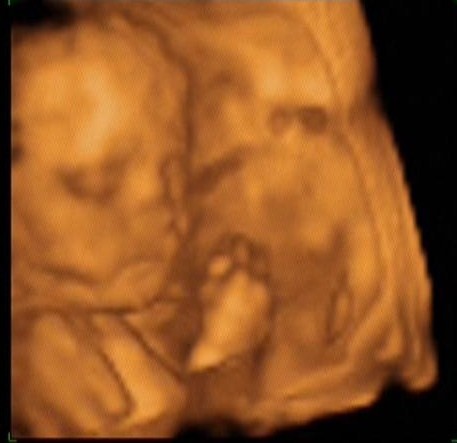

Kép kisfiunk

Kép

szóval: jajj, de gyönyörűűűűűséges :lol: a nózi és a szája olyan, mint apukájának! állítólag daliás legény lesz szép hosszú combokkal :lol: jelenleg 1100gramm :shock: azt mondta a hölgy, h vagy nagy baba, vagy majdnem két héttel idősebb, mint a mensi mutatja :lol: ha a 26hetet vesszük figyelembe, akkor a méretei alapján inkább 4kg és feletti lesz majd 40hétre :lol: :lol: :lol:

és a lényeg: a vesetágulat stagnált, a 4héttel ezelőtthöz képest szerencsére nem nőtt! ennek nagyon örülünk!!!!!!!!!!!!

edi: jajj, ne tudd meg hogy olvadoztunk!!!!!!!! édes virágszálunk kezét-lábát-kölödzsinórt pakolgatta arcocskája elé, lábujjait bekapta :lol: mindent próbált, csak a pofiját ne lássuk!!! de kitartó volt a hölgy, addig próbálkozott, böködte-nyomkodta-köhögtetett-forgatott az ágyon míg meg nem láttuk!